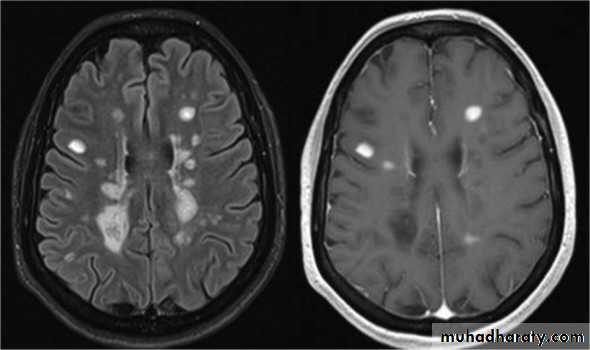

MRI :characteristic abnormalities are found in >95% of patients, although more than 90% of the lesions visualized by MRI are asymptomaticLesions are frequently oriented perpendicular to the ventricular surface,(Dawson’s fingers)

Lesions larger than 6 mm located in the corpus callosum, periventricular white matter, brainstem, cerebellum, or spinal cord are particularly helpful diagnostically